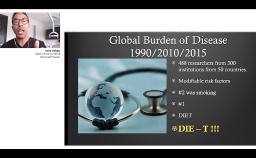

This lecture gives an overview of the relevant comparative anatomy and histology surrounding teeth and implants in healthy or pathologic conditions. Emphasis is placed on creating physiologic relationships and minimizing inflammation. The influence of factors such as the implant-abutment interface, timing of loading, surface characteristics, and the presence of inflammation are discussed based on current evidence.